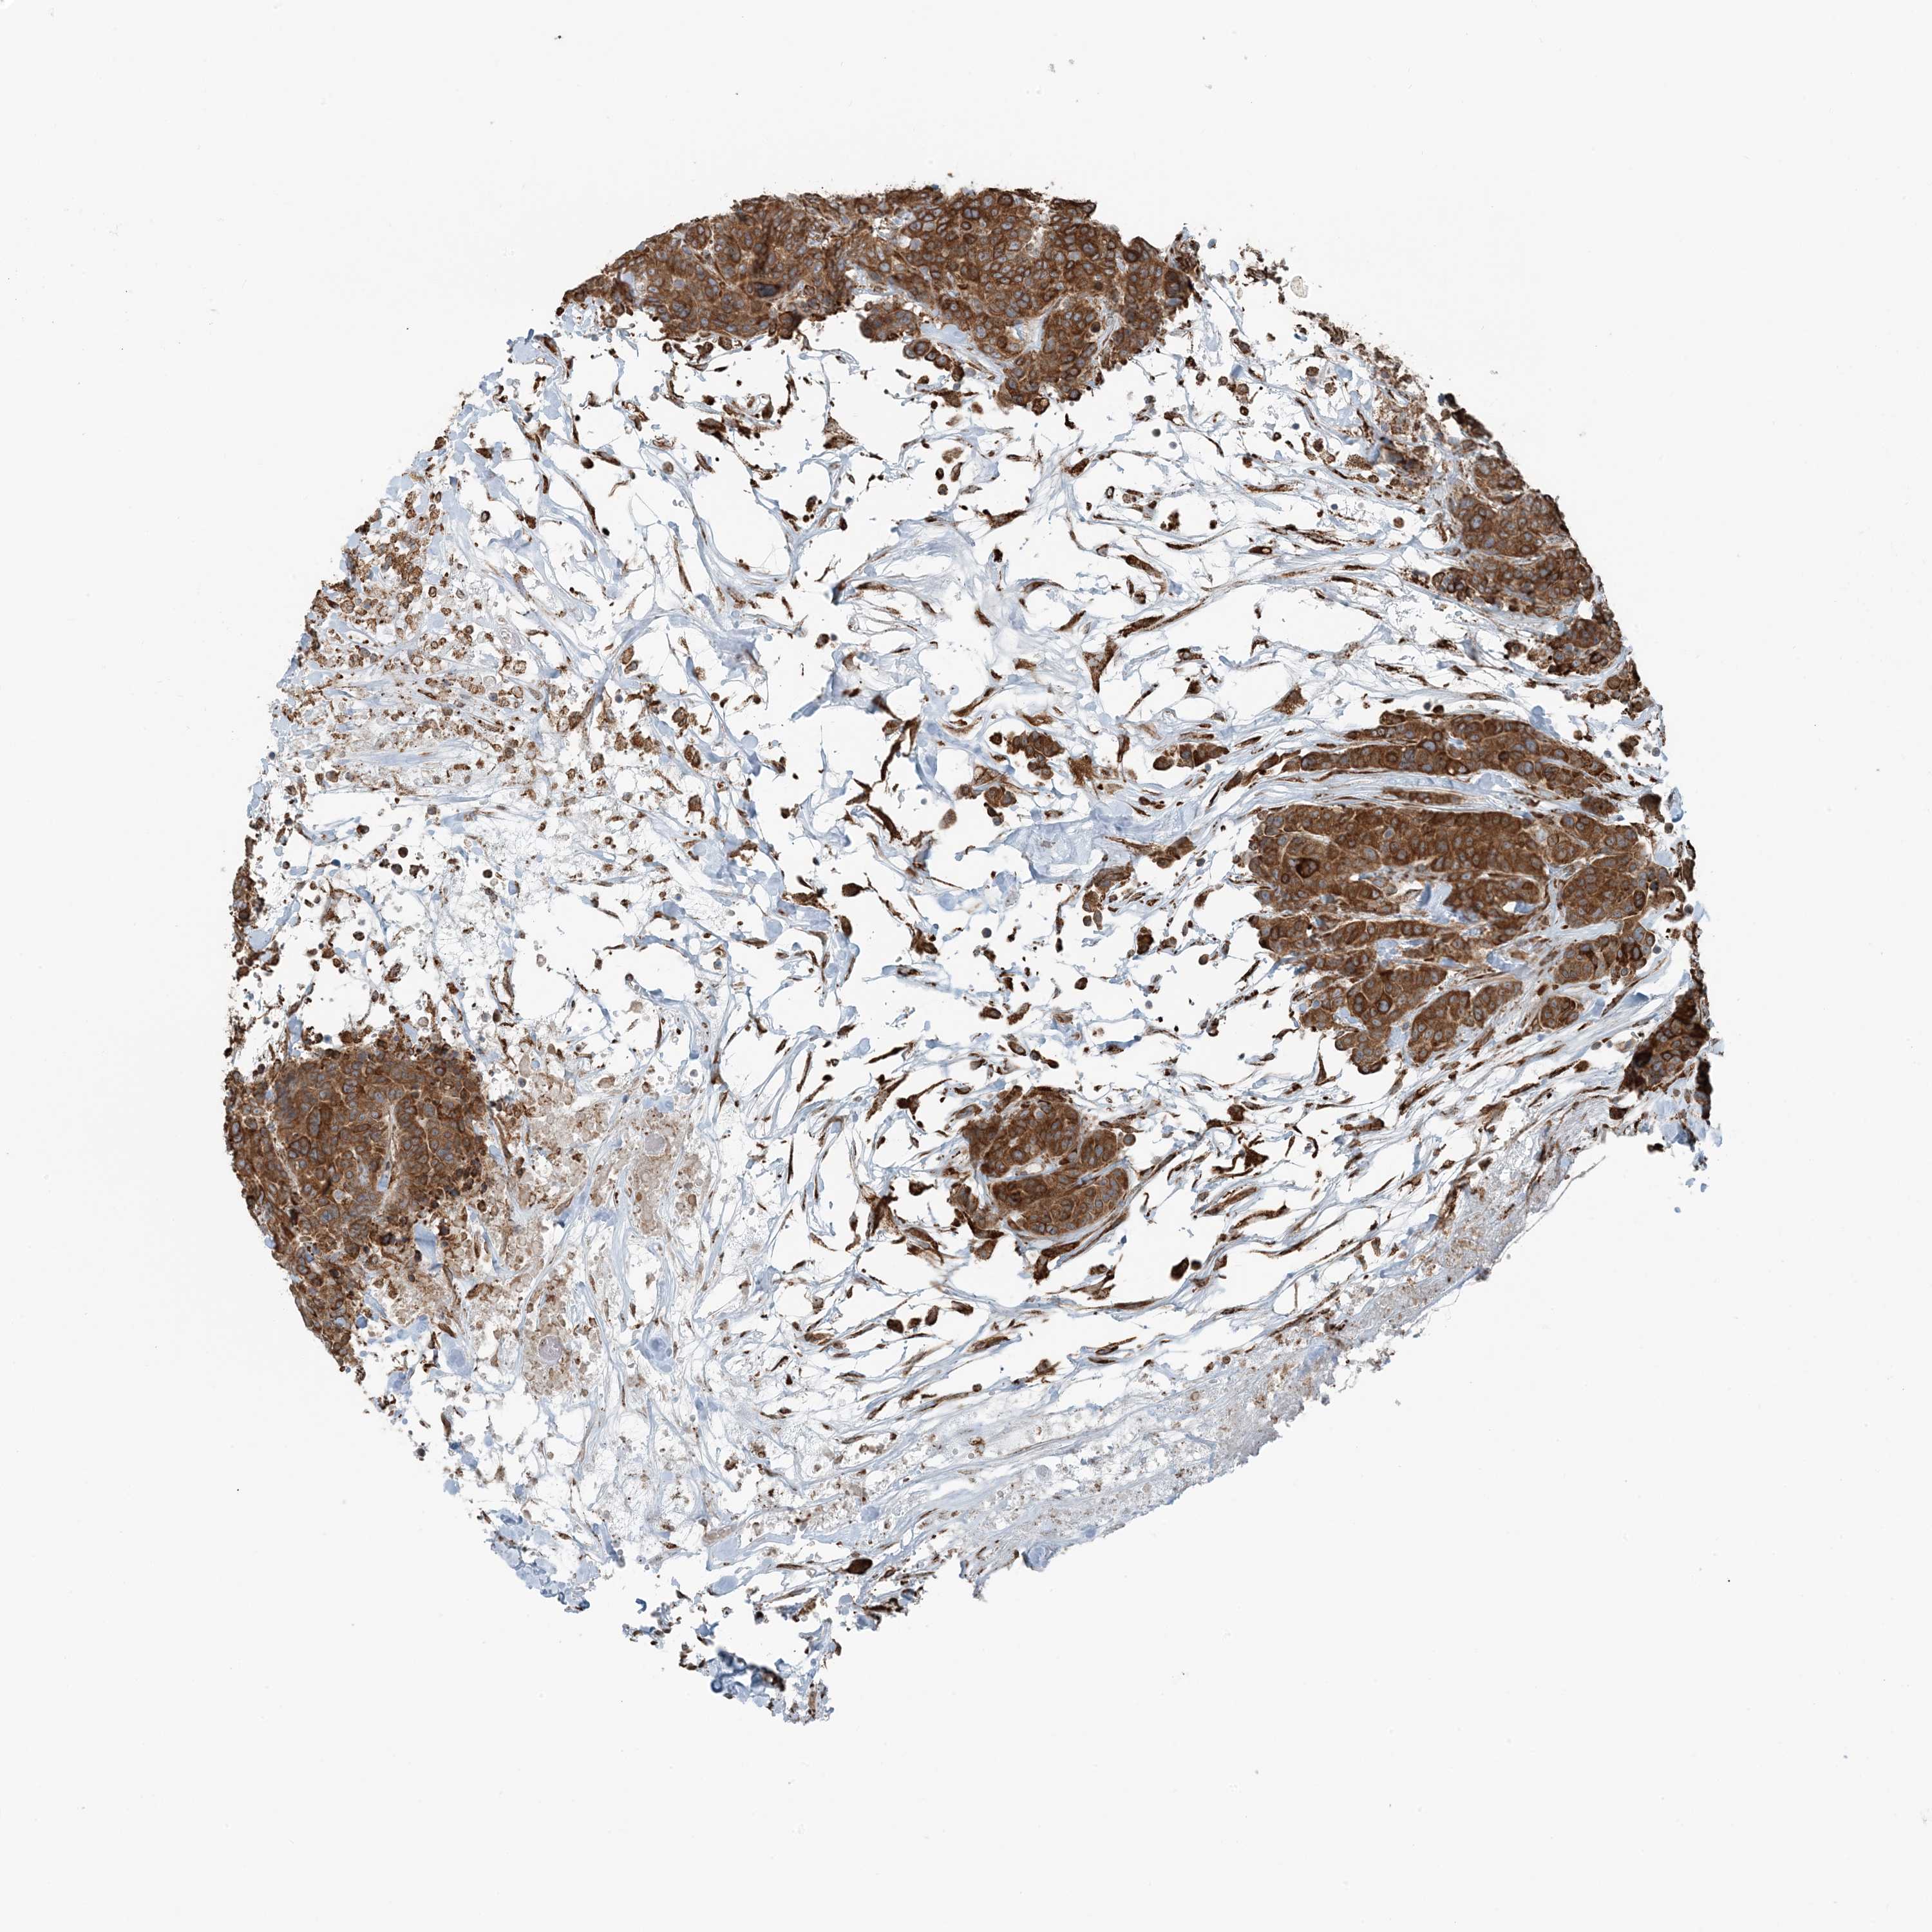

CANCER BREAST CANCER Show tissue menu

BRCA TCGA BRCA VALIDATION PROTEIN EXPRESSION